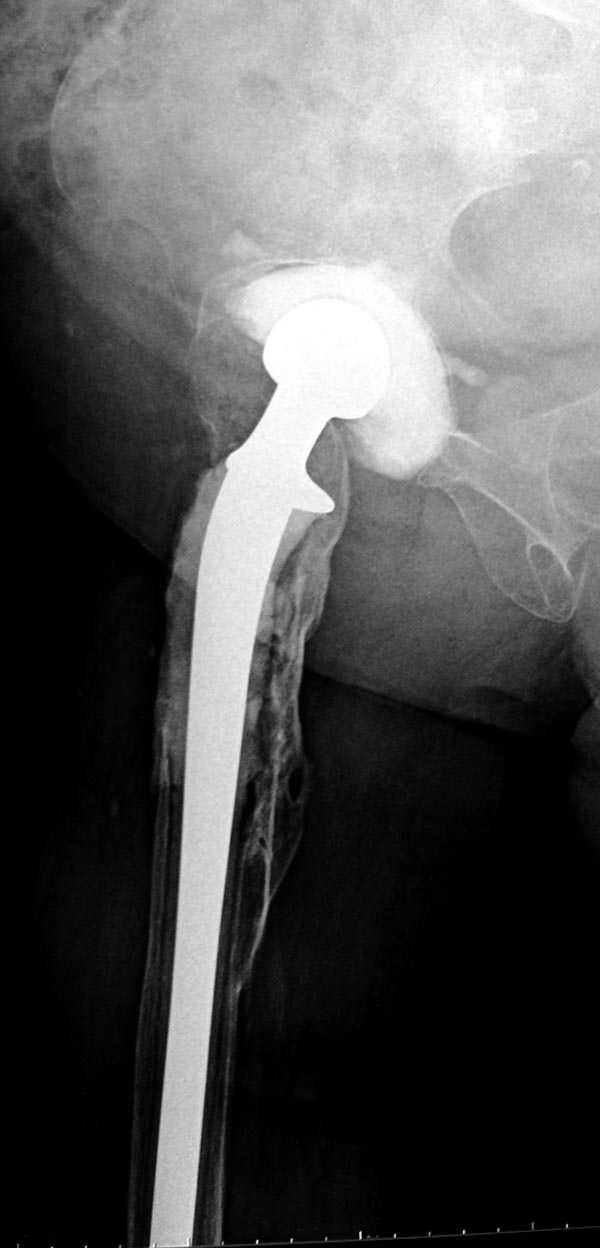

Вот снимки по свежей ситуации, парень 19 лет, длинный оскольчатый перелом бедра от шейки до в-с/3. давно уже ходит на своих ногах.

Делалось не мной (ассистировал), я на тазах "пока ещё не волшебник, а только учусь"

Представленные Вами рентгенограммы действительно являются примером качественной фиксации спице-стержневым аппаратом. Они, как ни что другое, многое иллюстрируют.

Кроме того, было бы ошибкой ставить знак равенства между нашим и Вашим пациентами. Они не только не похожи, разница между ними просто огромная. Говорю это не для того, чтобы задеть Вас или обидеть. Ни в коем случае. Просто теперь я понимаю, что Ваше мнением строится на простом преломлении Ваших подходов к лечению пациентов со свежими переломами, на ситуацию, абсолютно несопоставимую, подобную нашей.